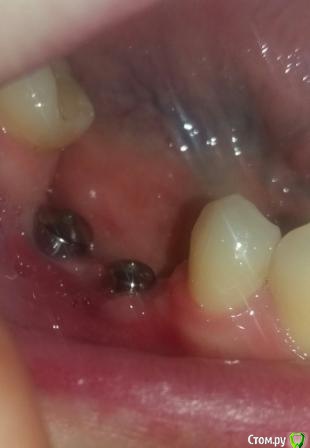

Oksana-p Опубликовано 15 июня, 2016 Автор Поделиться Опубликовано 15 июня, 2016 Вот такая ситуация сейчас..... Ссылка на комментарий

Oksana-p Опубликовано 25 июля, 2016 Автор Поделиться Опубликовано 25 июля, 2016 ДД. Коронки с розовой десной опять не понравились ортопеду. Очень уж длинные коронки получаются. Не знает, что со мной делать... Пытается как-то выкрутиться. Да за эти 2,5 месяца после пересадки десны похоже ничего от нее не осталось. Скоро опять будет виден верх импланта. А такой кусок вырезали... Вот фото сейчас во рту. Другой ортопед предложил два варианта - сделать опять пластику десны (хотя там мало что осталось) или удалить эти импланты, сделать костную пластику и т.д. Но в Минске не знаю куда обращаться. В клинике, где мне ставили, тот хирург уже уволился. Да они и не хотят ничего переделывать, т.к. считают что у меня все отлично. Ув. форумчане, посоветуйте что лучше сделать. Ссылка на комментарий